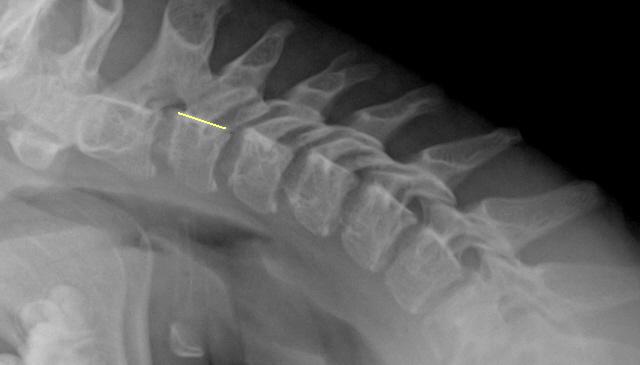

Речь идет не о "подвижности в суставе", а о нестабильности в сегменте. Задний контур С3 помечен "желтым". Обратите внимание, как смещаются позвонки в положении сгибания и разгибания с учетом "заднего контура".